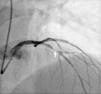

Case reportThe patient is a 41-year-old male with a history of hypertension, smoking (20 pack-years) and dyslipidemia (prior tests showed an LDL of 107 mg/dl), with no family history of coronary artery disease. He had an NSTEMI on March 4, 2016 as the first symptom of coronary artery disease. He underwent cardiac catheterization around 12 hours after admission to the hospital. The procedure revealed the presence of coronary artery disease extensively involving several segments of the circumflex artery (Cx), with 50% ostial stenosis associated with a 70-90% lesion at the bifurcation to the outlet of the first obtuse marginal branch (OM1), as well as a 70-90% lesion in the ramus intermedius. A mild lesion was found in left anterior descending artery (LAD), with less than a 30% reduction in the lumen (Figure 1). During the same procedure, angioplasty was performed on the Cx/OM1 and ramus intermedius lesions with placement of a drug-eluting stent in each lesion, with good angiographic result and no complications. No further ischemic events were recorded during hospital stay. The patient was discharged three days after the procedure, with a peak troponin I value of 0.88 ng/ml (normal value <0.04) and a peak CRP value of 4.3 mg/l (normal value <5.0). His outpatient medication was aspirin 100 mg once daily, perindopril 5 mg/amlodipine 5 mg once daily, carvedilol 6.25 mg twice daily and atorvastatin 20 mg once daily. Ticagrelor 90 mg twice daily was also recommended, which the patient refused due to financial constraints, so he was medicated with clopidogrel 75 mg once daily. The only significant transthoracic echocardiography finding was hypokinesis of the distal segment of the inferolateral wall, with preservation of left ventricular systolic function (calculated ejection fraction: 55-60%).

Coronary angiography with a 30% lesion in the middle segment of the LAD (white arrow). A circumflex artery (Cx) with 50% ostial stenosis, 70-90% lesion at the bifurcation to the outlet of the first obtuse marginal branch (OM1), as well as a 70-90% lesion in the ramus intermedius were found.